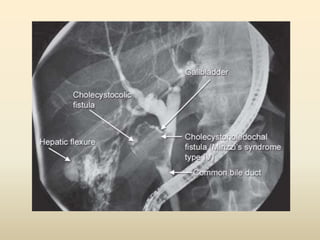

ERCP

• The diagnostic accuracy of Mirizzi syndrome

with this method reaches around 55% to 90%

• The features of ERCP in Mirizzi syndrome

– narrowing or curvilinear extrinsic compression

involving the lateral portion of the distal common

hepatic duct with proximal ductal dilatation and

normal distal caliber

ERCP • The diagnosticaccuracy of Mirizzi syndrome with this method reaches around 55% to 90% • The features of ERCP in Mirizzi syndrome – narrowing or curvilinear extrinsic compression involving the lateral portion of the distal common hepatic duct with proximal ductal dilatation and normal distal caliber